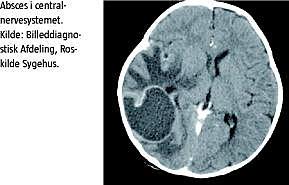

Initialt var der et godt behandlingsrespons, men på femte døgn blev patienten højfebril og fik hovedpine samt leukocytstigning. Ny lumbalpunktur viste 2.100 celler × 109 /l, og akut computertomografi (CT) af cerebrum viste en stor højresidig parietooccipital absces på fem centimeter i diameter med overskydning af midtlinjestrukturer samt mindre abscescavitet temporalt. Der udtømtes 43 ml pus ved neurokirurgisk intervention. Dyrkning af abscesmateriale var negativ efter fem døgn. Der blev både kørt realtids-PCR og 16-S-PCR på CSV og abscesmateriale, og begge viste DNA-kopier af S. pneumoniae. Ved latexagglutinationstest [1], der blev gennemført direkte på klinisk materiale (CSV og abscesmateriale), blev der påvist en positiv kapselreaktion for pneumokokserotype 3, der ikke er dækket af vaccinen. Ekkokardiografi samt immunologisk screening viste intet abnormt.